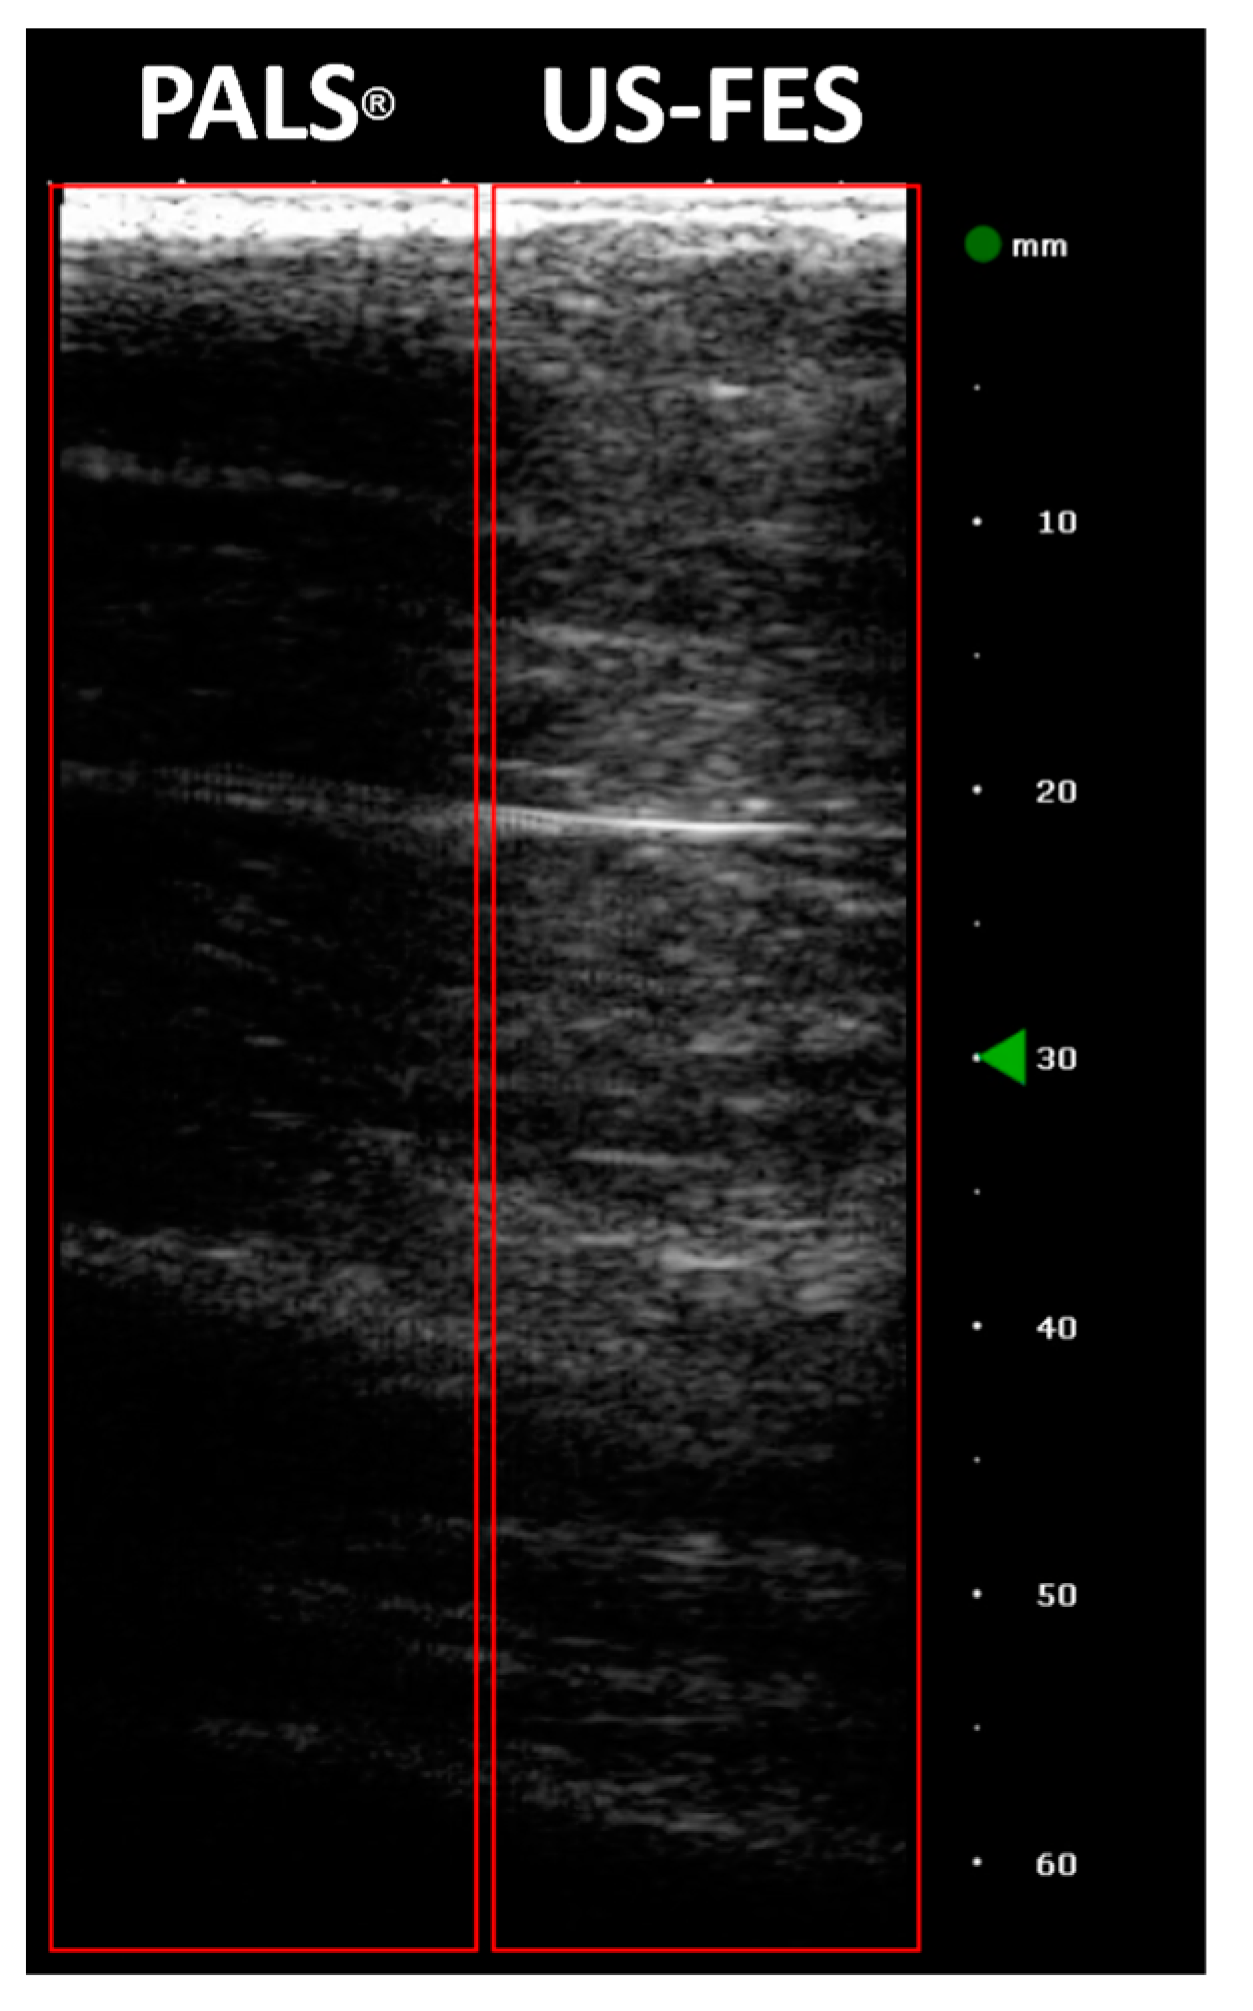

3.3. Feasibility of US-Compatible FES Electrode with B-Mode Imaging